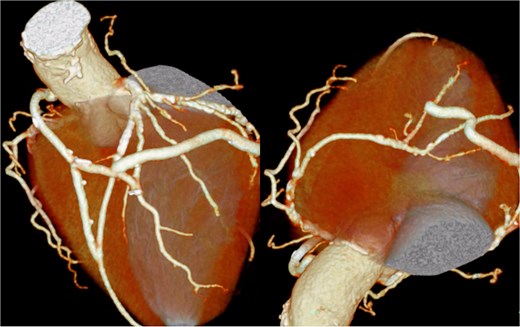

Preoperative 3D CT angiography of the entire vasculature. Preoperative 3D CT angiography image of the entire vasculature demonstrates that the ITAs are an important source of blood flow to the lower limbs.

The patient underwent median sternotomy, and the non-touch SVG was harvested from the right leg. Cardiopulmonary bypass via the area around the origin of the brachiocephalic artery and the right atrium was established using the Seldinger technique. The proximal anastomosis of the SVG was performed on the right lateral wall of the ascending aorta using the Heartstring III Proximal Seal System (Maquet Cardiovascular LLC, Getinge AB, Rastatt, Germany), and exposure was facilitated by a stabilizer. The SVG was anastomosed to the left anterior descending artery, and another SVG segment was joined end-to-side to construct a T-composite graft. Then, the T-composite SVG was sequentially anastomosed to the diagonal branch, obtuse marginal branch, atrioventricular branch, and posterior descending branch. However, torsion caused narrowing of the SVG just distal to the diagonal anastomosis; therefore, a clip was applied, and the SVG was divided at that site. Then, the distal segment of the SVG was re-anastomosed end-to-side to the SVG that had been anastomosed to the diagonal branch (Fig. 4) (Video 1). After completion of the anastomoses, the patient was weaned from cardiopulmonary bypass, and surgery was completed. The postoperative course was uneventful, and the patient was transferred to another hospital for rehabilitation on postoperative day 28. At ~2 years after surgery, the patient was free from heart failure recurrence. Because symptoms of lower limb ischemia did not develop, revascularization of the lower limbs was not performed.

Postoperative coronary 3D CT angiography. Postoperative cardiac 3D CT image showing the final graft configuration. A SVG was anastomosed to the left anterior descending artery. Another SVG segment was joined end-to-side to construct a T-composite graft. This composite SVG was sequentially anastomosed to the diagonal branch, obtuse marginal branch, atrioventricular branch, and posterior descending branch. After revision because of torsion just distal to the diagonal anastomosis, the distal SVG segment was re-anastomosed end-to-side to the SVG connected to the diagonal branch, resulting in the final graft arrangement demonstrated in this image.